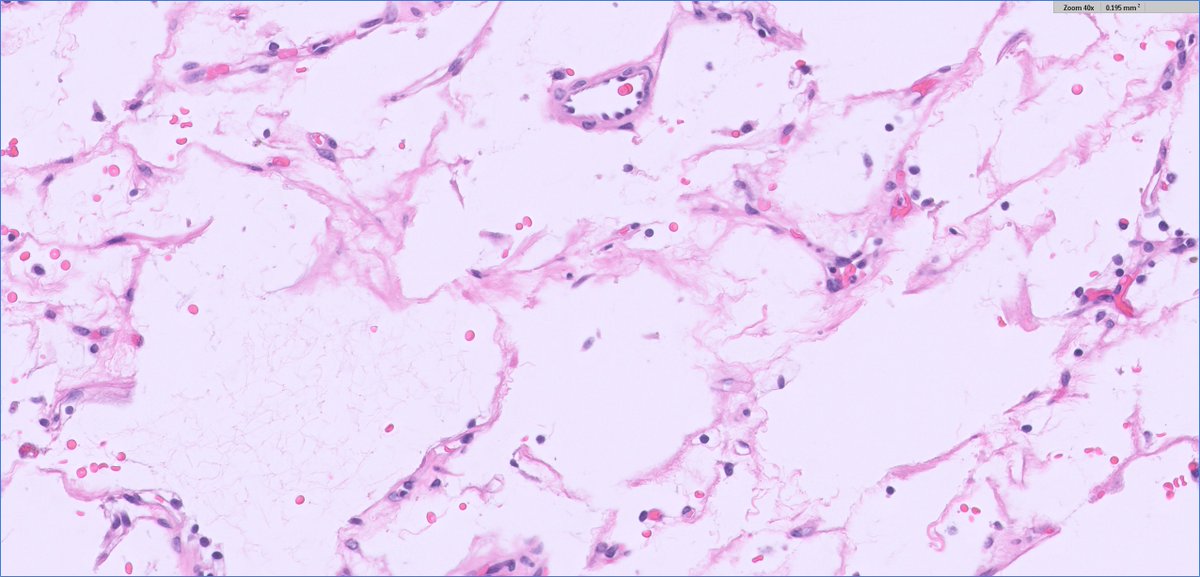

Ever seen a viral party in your skin? Say hello to molluscum contagiosum! Under the microscope 🔬.It's all about the Henderson-Patterson bodies—giant, eosinophilic inclusion bodies packed with viral DNA like little viral hoarders. #Dermpath #pathology

Ever seen a viral party in your skin?

Say hello to molluscum contagiosum! Under the microscope 🔬.It's all about the Henderson-Patterson bodies—giant, eosinophilic inclusion bodies packed with viral DNA like little viral hoarders.

#Dermpath #pathology